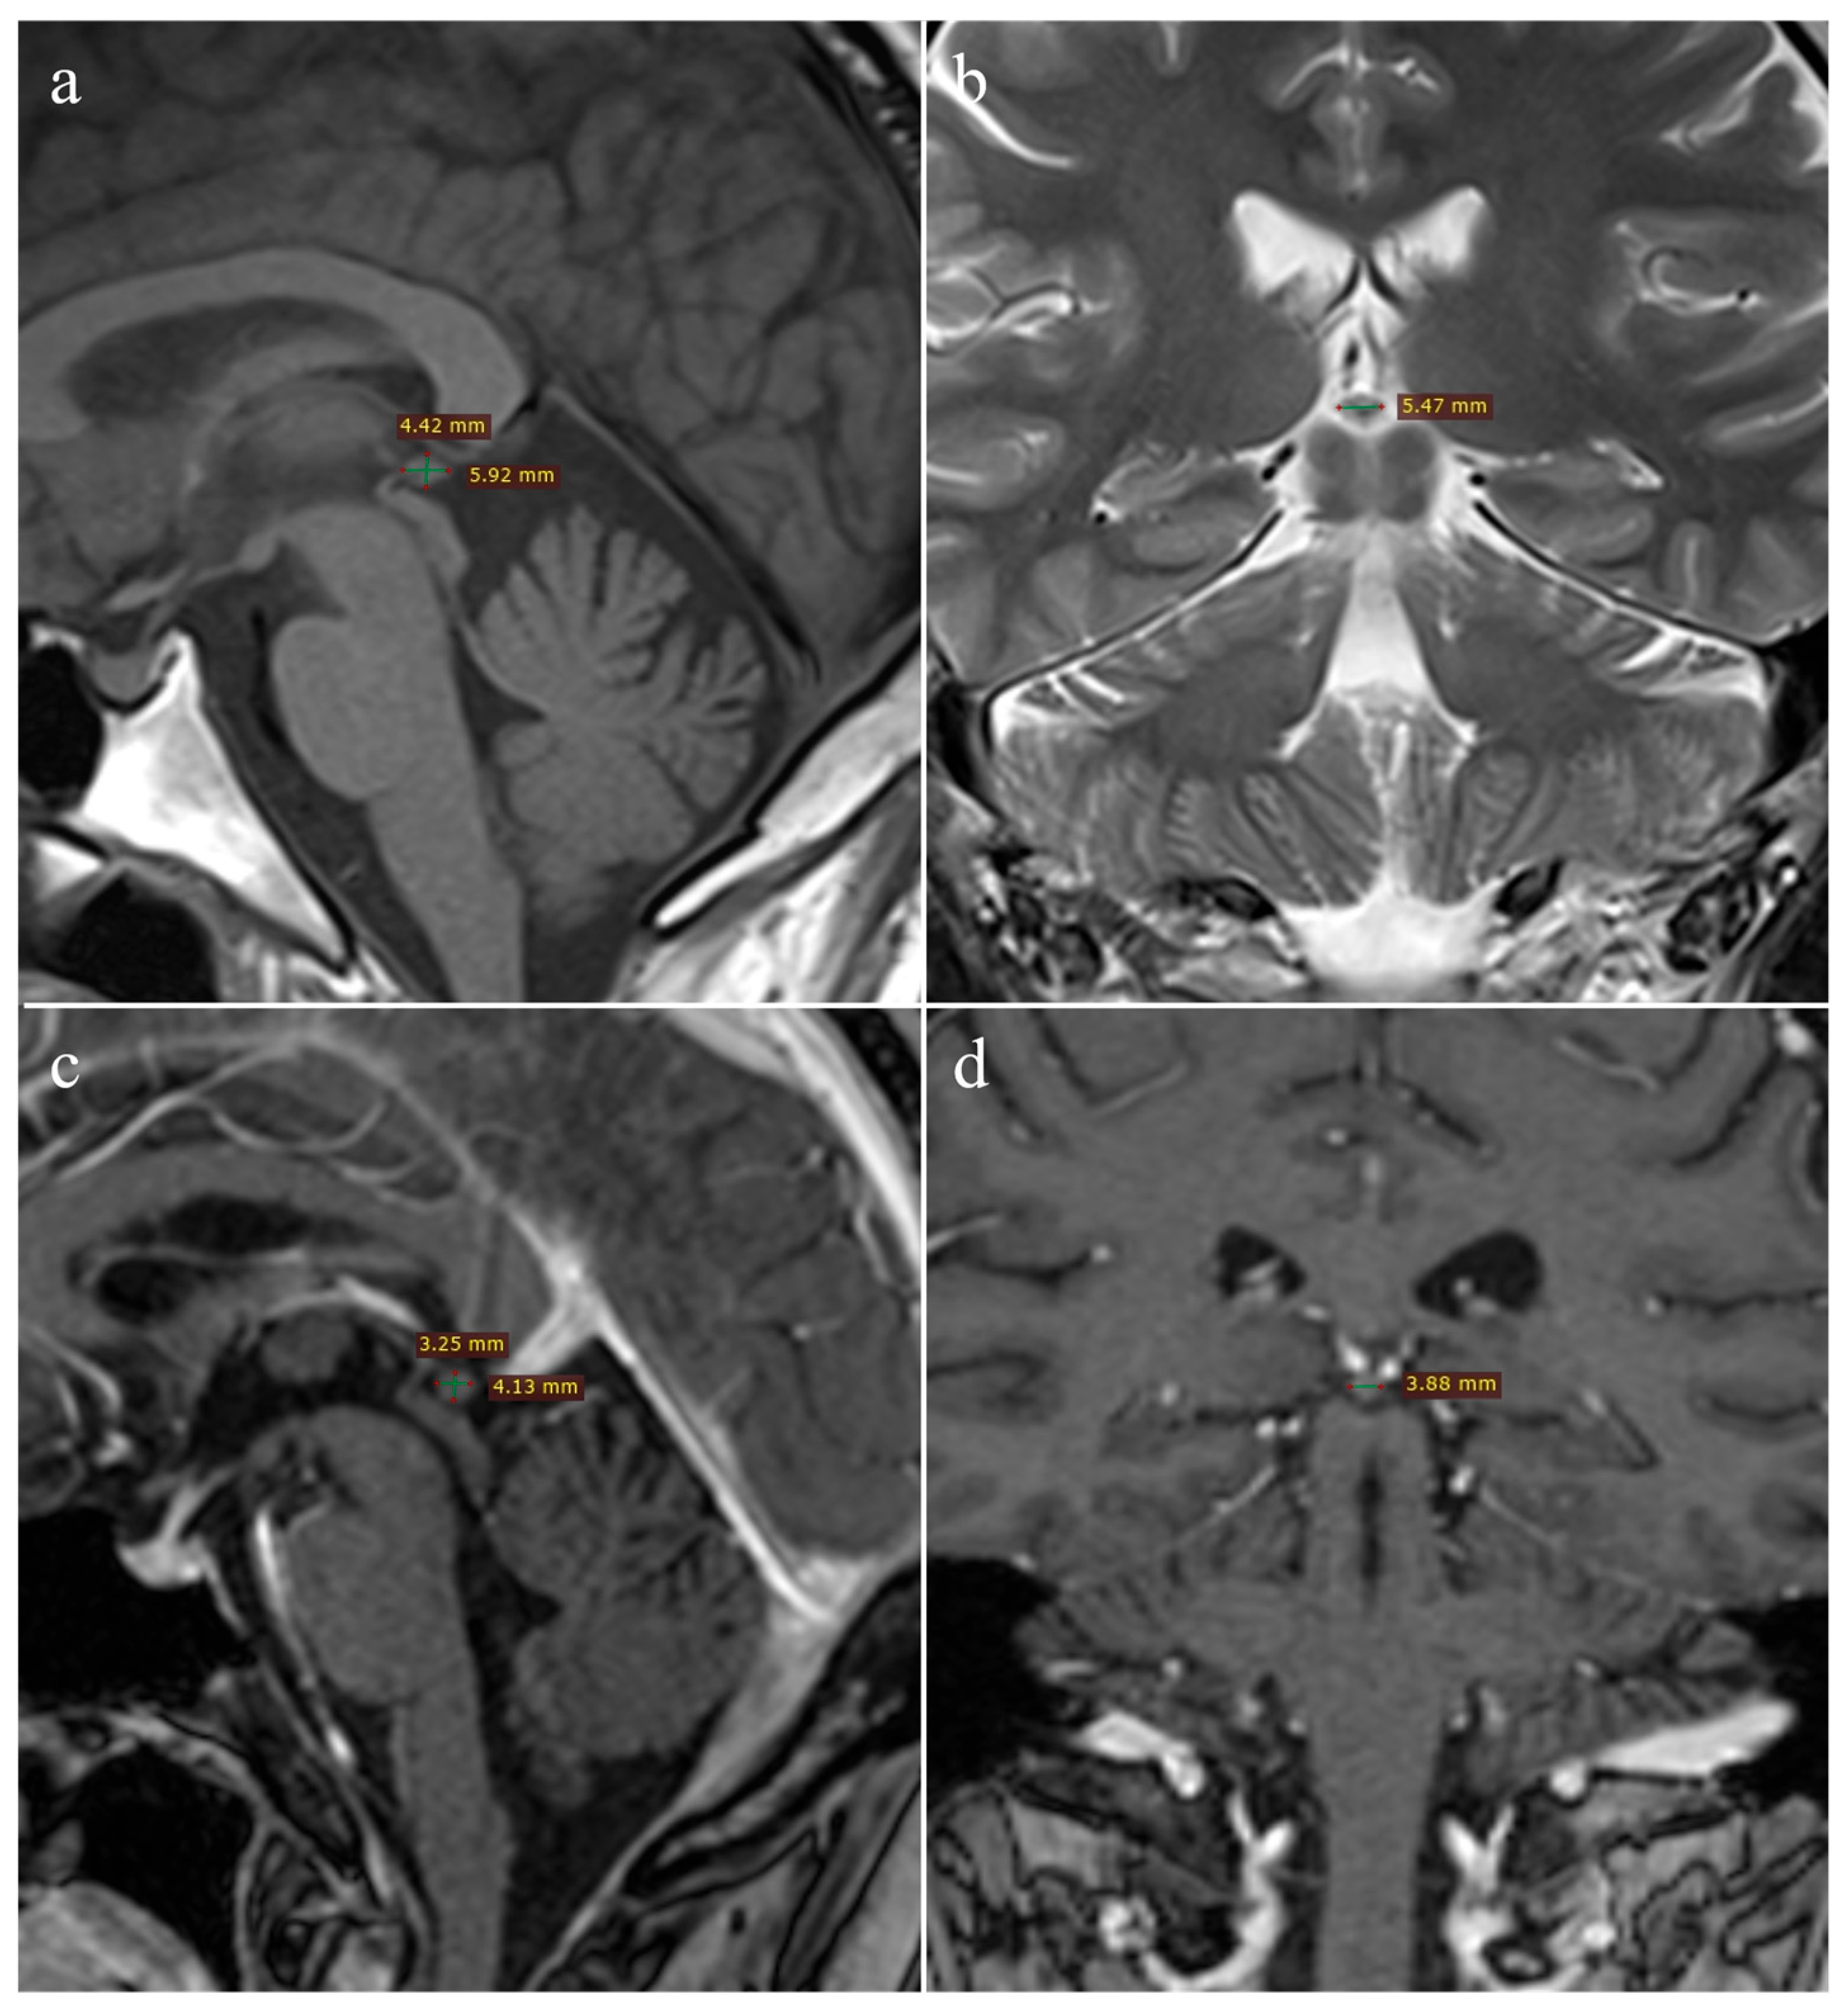

2.4. Imaging Analysis

3.2. Differences in Volume Between Oncology Patients and Healthy Controls